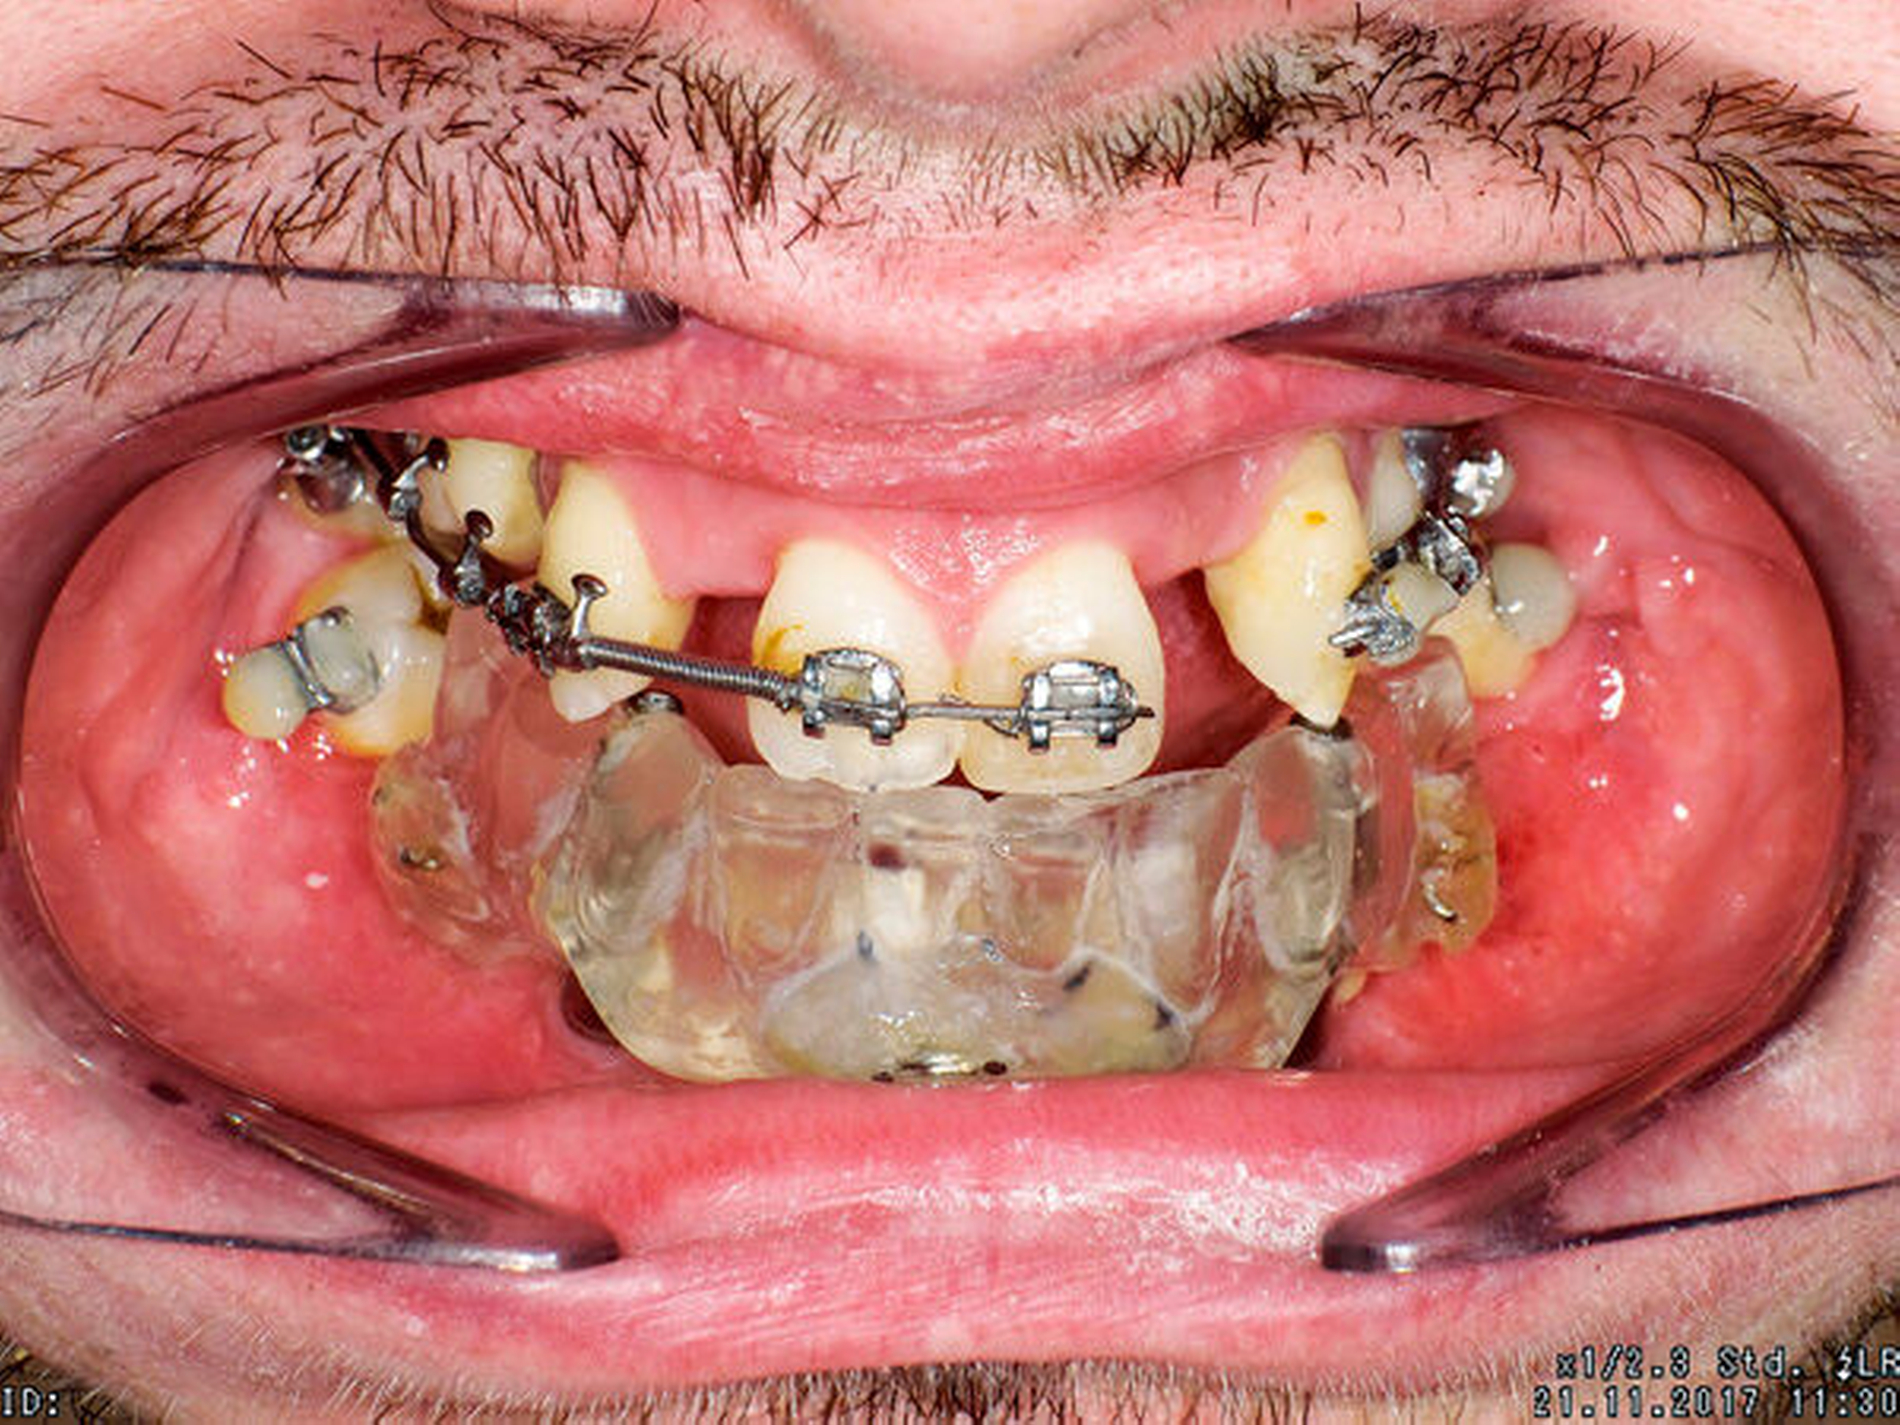

Zu Therapiebeginn im Alter von 20 Jahren zeigte sich eine skelettale Klasse III mit transversaler, vertikaler und sagittaler Unterentwicklung der Maxilla. Im Oberkiefer war die Zahnanzahl deutlich reduziert. Der Unterkiefer war nahezu zahnlos, hier waren außerdem der Alveolarfortsatz und die attached Gingiva stark atrophiert (Abbildungen 1 bis 3).

Vor der prothetischen Rehabilitation war dementsprechend eine kieferorthopädische und kieferchirurgische Vorbehandlung mit dem Ziel der dreidimensionalen skelettalen und dentalen Harmonisierung zwingend indiziert. Zunächst wurden die kariös zerstörten Zähne 14, 22 und 36 sowie die verlagerten Zähne 24 und 38 entfernt. Im Oberkiefer wurde eine kieferorthopädische Therapie eingeleitet, um den Zahnbogen auszuformen. Hierbei wurde eine Lückenöffnung in den Regiones 012 und 022 mit Protrusion der Zähne 11 und 21 vorgenommen. Im Anschluss konnte schließlich im Unterkiefer eine interforaminäre Insertion von vier Implantaten erfolgen (Abbildung 4).

Anschließend wurde eine bimaxilläre Umstellungsoperation (in der Le-Fort-I-Ebene und nach Obwegeser/Dal Pont) durchgeführt (Abbildung 5). Hierfür wurde für den OP-Splint eine provisorische Implantat-getragene Prothese im Unterkiefer angefertigt, so dass die Implantate letztlich auch zur Eingliederung des OP-Splints dienten (Abbildungen 6 und 7). Zusätzlich konnte postoperativ durch die Implantat-getragene Prothese die Okklusion gesichert und das Risiko eines Rezidivs im Sinne einer Okklusionsverschiebung minimiert werden [Ohba et al., 2015].